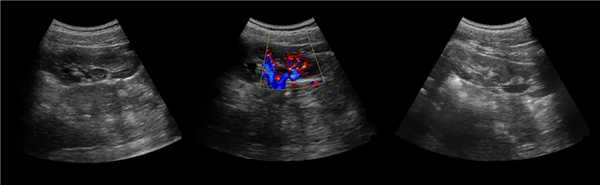

Рисунок. На УЗИ округлое образование разделяет почечный синус на два сегмента с общей лоханкой; междолевые артерии огибают образование; эхогенность и интенсивность сосудистого рисунка внутри близка корковой зоне. Заключение: Гипертрофия колонны Бертини или неполная паренхиматозная перемычка. Это вариант нормального строения почки. Термин «неполное удвоение ЧЛК» неверный, т.к. неполная паренхиматозная перемычка не является признаком удвоения ЧЛК.

Рисунок. На УЗИ синус почек широкий, неоднородной эхоструктуры (1, 2). На фоне гиперэхогенного жира гипоэхогенный очаг округлой формы (2), при ЦДК междолевые сосуды проходят через гипоэхогенную зону без смещения (3) — это гипоэхогенный жир. При ожирении липоматоз синуса можно ошибочно принять за атрофию паренхимы.